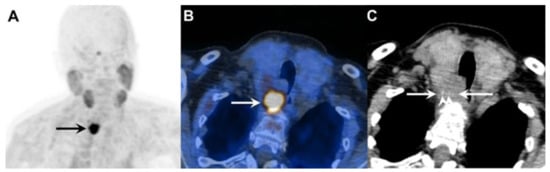

In addition, parathyroid tissue—both benign and malignant—may express somatostatin receptors (SSTR) [78]. A study by Storvall et al. demonstrated SSTR expression across all parathyroid tumor subtypes—including typical adenomas, atypical adenomas, and PCs—predominantly within the cytoplasm rather than on the cell membrane. Among receptor subtypes, SSTR 1 showed uniform expression, while SSTR 2–5 varied by tumor type. Notably, PC exhibited consistently high levels of SSTR expression, particularly SSTR 5, while adenomas demonstrated only minimal expression. The marked difference in cytoplasmic SSTR 5 expression rates between parathyroid tumors may serve as a potential malignancy indicator [79]. These findings support the biological rationale for SSTR-based imaging [80] and potential theranostic applications using peptide receptor radionuclide therapy (PRRT) (Figure 5).

Figure 5. Metastatic parathyroid carcinoma on [18F]FDG PET/CT and [68Ga]Ga DOTA-TATE PET/CT. Legend: A 72-year-old patient with metastatic parathyroid carcinoma. He had elevated Ca levels of 13.5 mg/dL (8.8–10.6 mg/dL) and PTH levels of 11,663 (12–88 pg/mL) after repeated surgeries and tyrosine kinase inhibitor therapy. [18F]FDG PET/CT shows extensive pleural metastases ((A), whole-body MIP image, black arrow; (B), axial MIP; (C), PET/CT, white arrow). [68Ga]Ga DOTA-TATE PET/CT was acquired to evaluate options for peptide receptor radionuclide therapy ((D), whole-body MIP image; (E), axial MIP; (F), PET/CT). Unfortunately, there was a faint uptake lower than the physiological liver uptake, rendering the patient ineligible for PRRT.

However, clinical evidence remains limited. At present, SSTR imaging is not recommended as a standard diagnostic tool in PC but may be considered selectively in patients with high receptor expression where PRRT is being contemplated as a therapeutic option (Figure 6).